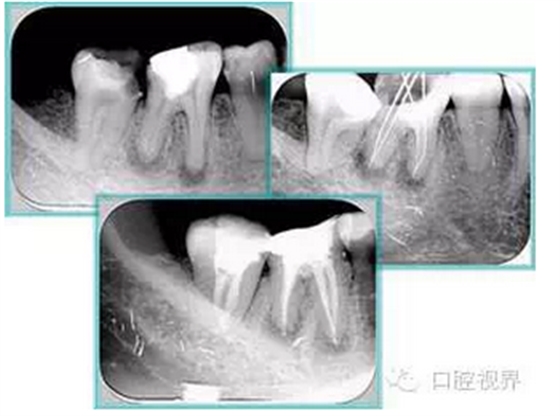

右圖及下圖為器械折斷的 X 線片。箭頭處示折斷器械。

右圖箭頭處示臺階形成。